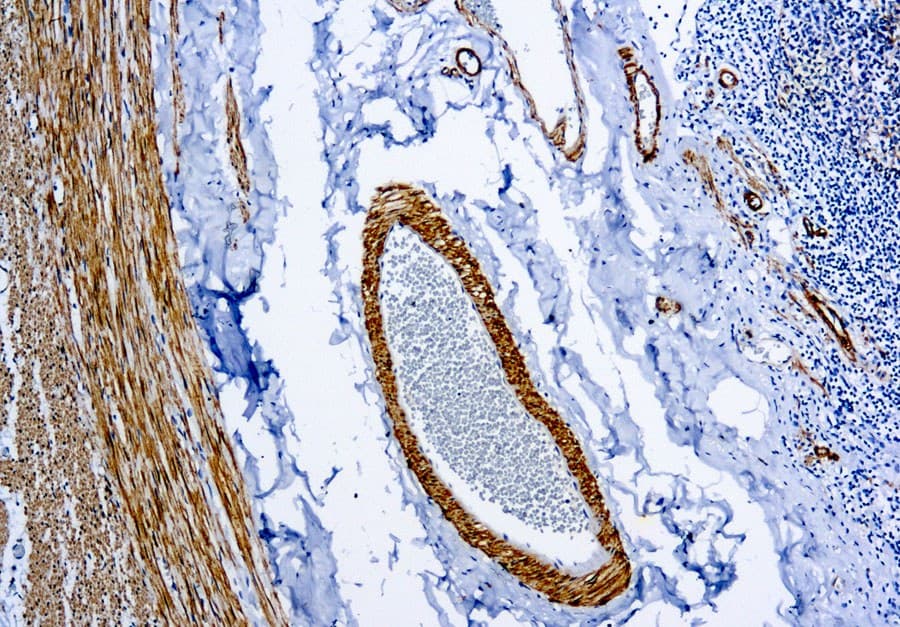

La miosina pesada de músculo liso (SM-MHC) es una proteína contráctil que se expresa selectivamente en células musculares lisas diferenciadas y células mioepiteliales. La detección inmunohistoquímica de SM-MHC proporciona alta especificidad para la diferenciación de músculo liso y, por lo tanto, ayuda a los patólogos a distinguir tumores verdaderos de músculo liso de imitadores histológicos. En patología mamaria, SM-MHC se considera un marcador mioepitelial confiable, particularmente útil al evaluar lesiones proliferativas o esclerosantes complejas en las que la presencia o ausencia de una capa de células mioepiteliales determina el diagnóstico.

- Identificación de capas intactas de células mioepiteliales que rodean conductos y lobulillos en lesiones mamarias benignas y in situ

- Apoyo para excluir invasión estromal en casos de carcinoma ductal in situ, adenosis esclerosante y cicatriz radial

- Fuerte patrón de tinción citoplasmática que es fácil de interpretar en tejidos FFPE adecuadamente conservados

Debe tenerse en cuenta que se ha reportado ocasionalmente tinción no específica en células endoteliales y ciertos componentes estromales. Por esta razón, la interpretación de la tinción de SM-MHC siempre debe realizarse en conjunto con la histomorfología y marcadores inmunohistoquímicos adicionales.